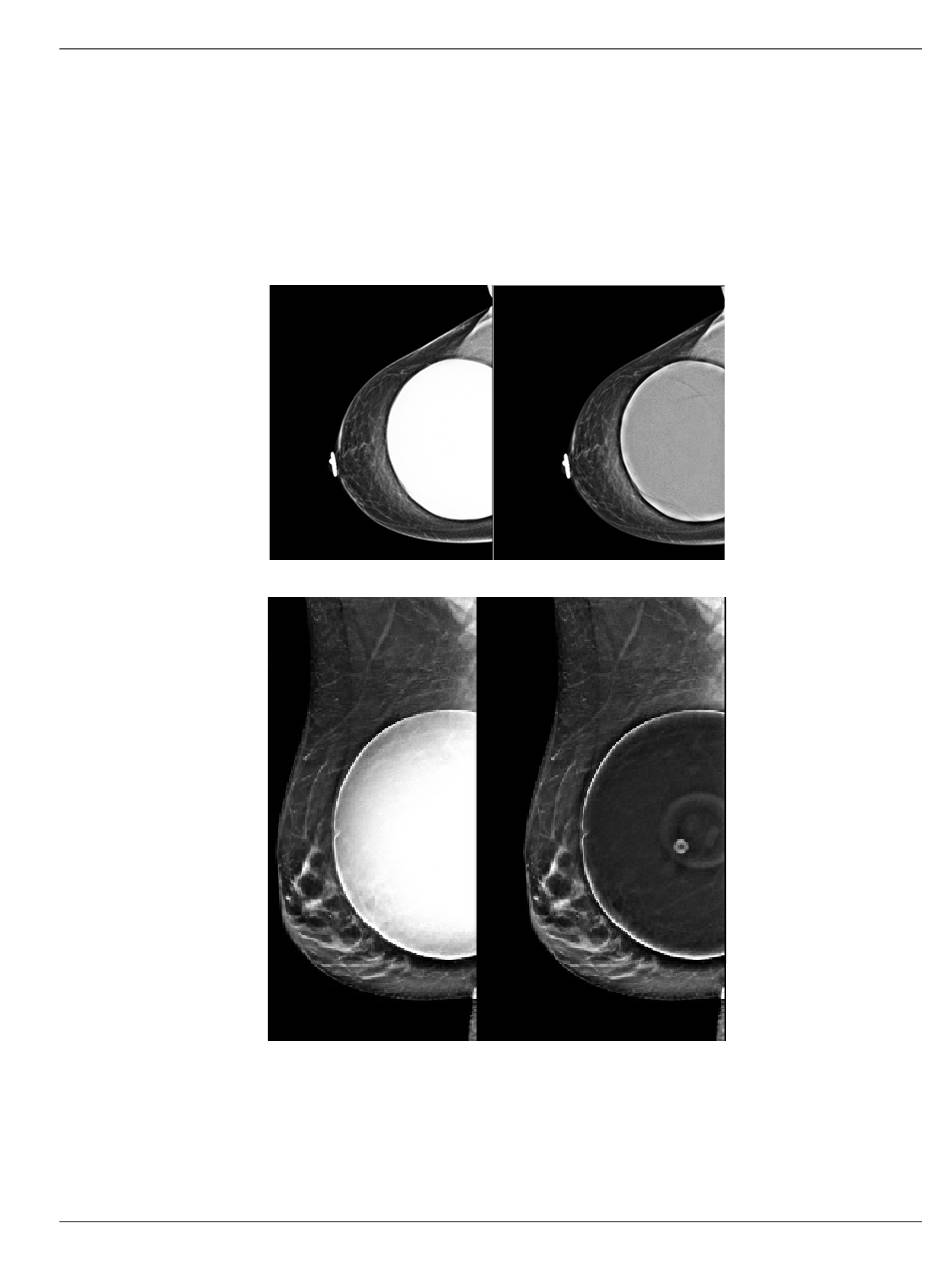

Eine optionale Bildverarbeitungseinstellung ist sowohl für die 2D- als auch für die 3D-

Bildgebung mit Implantaten verfügbar. Die Implantathelligkeit kann reduziert werden,

um die Sichtbarkeit des Grenzbereichs Implantat/Brust zu verbessern. Um diese Option

zu aktivieren, wenden Sie sich bitte an Ihren Hologic-Vertreter.

Abbildung 49: Vergleich der Standardhelligkeit und der reduzierten

Reduzierte Helligkeit

Helligkeit